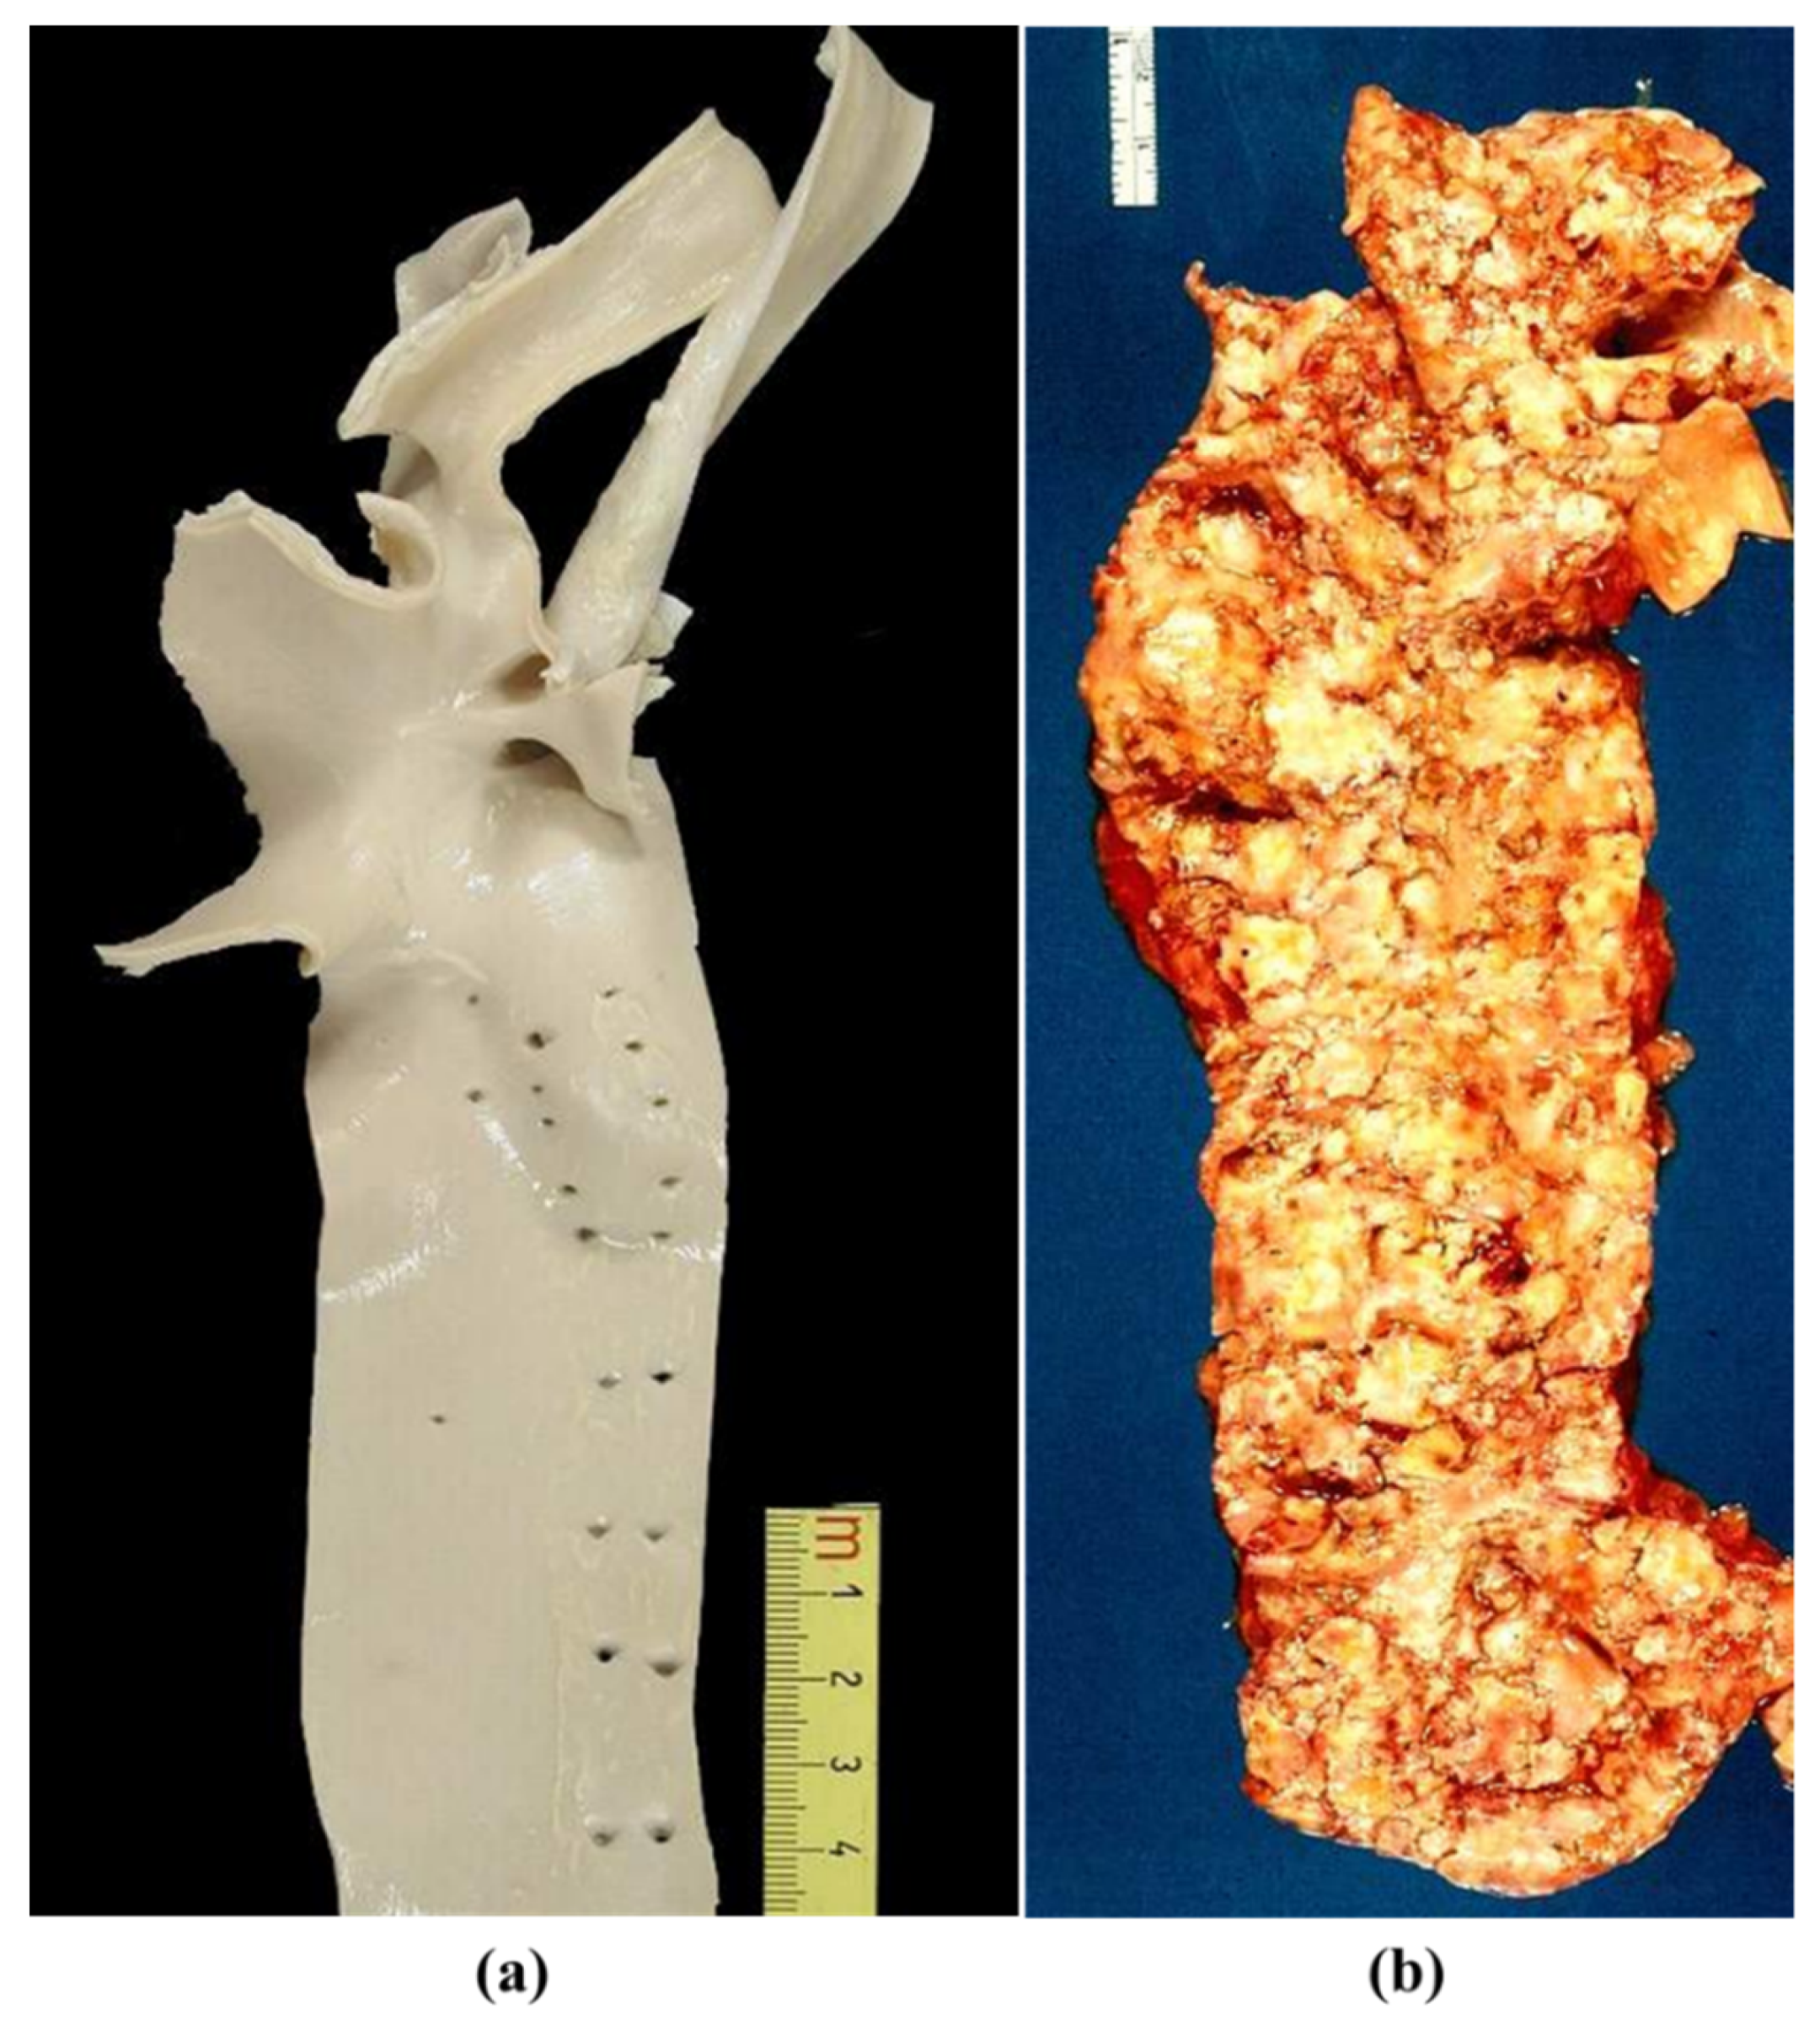

2. Normal Anatomy

3. Pathology

3.3. Degenerative Diseases of the Aorta

3.4. Inflammatory Diseases of the Aorta

3.5. Neoplasms

3.6. Thoracic Trauma